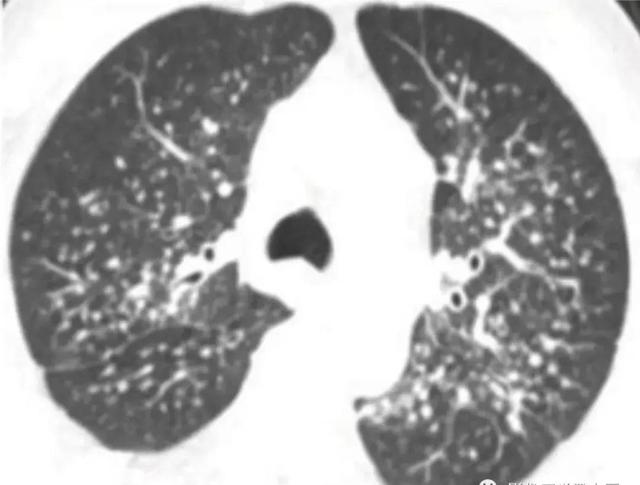

肺结核的分型诊断标准,肺结核的分型及影像学表现

急性粟粒型肺结核 CT肺窗,两肺可见分布均匀、大小均匀、密度均匀的粟粒状影,边界清晰